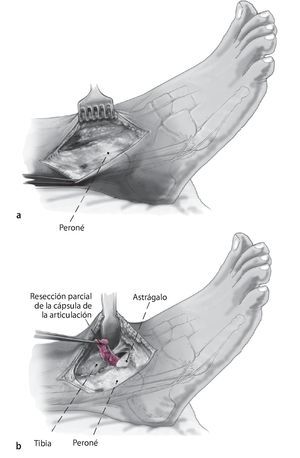

Fig. 3 Aborde el peroné desde un plano lateral en línea recta (a). La cápsula de la articulación se reseca parcialmente para dejar visible la sección tibioastragalina anterolateral (b). Realice una incisión en la vaina de tendón extensor y levante los tejidos blandos de la tibia en una sola capa. Ahora se puede colocar un separador de Hohmann para permitir una mejor visibilidad de toda la sección anterior del tobillo.